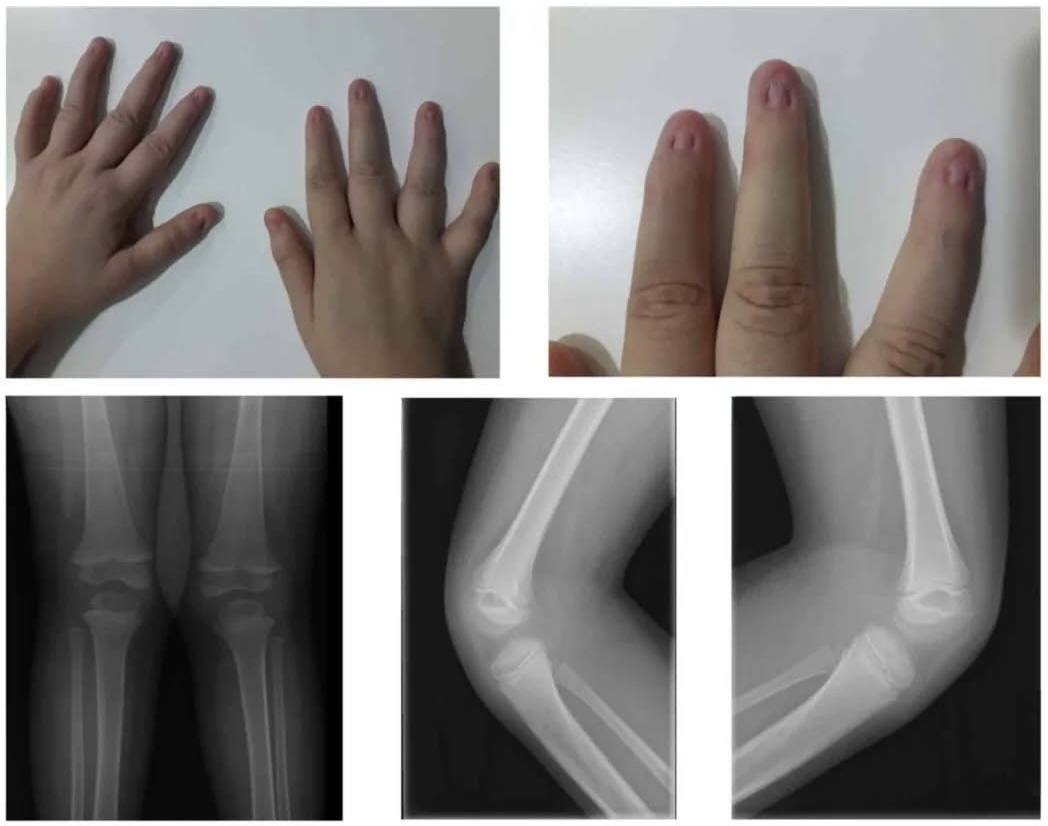

Микронихия – это уменьшение площади ногтевой пластины или просто ногти маленького размера. Чаще всего данная патология затрагивает не только размер, но и такие показатели, как толщина и рельеф ногтей. Часто наблюдаются и изменения цвета. При этом боковые и передний валики, наоборот, визуально увеличены в размерах, создавая определенный дисбаланс в эстетике.

Эта патология может проявляться как на руках, так и на ногах, причем на ногах она чаще всего затрагивает третий, четвертый и пятый пальцы.